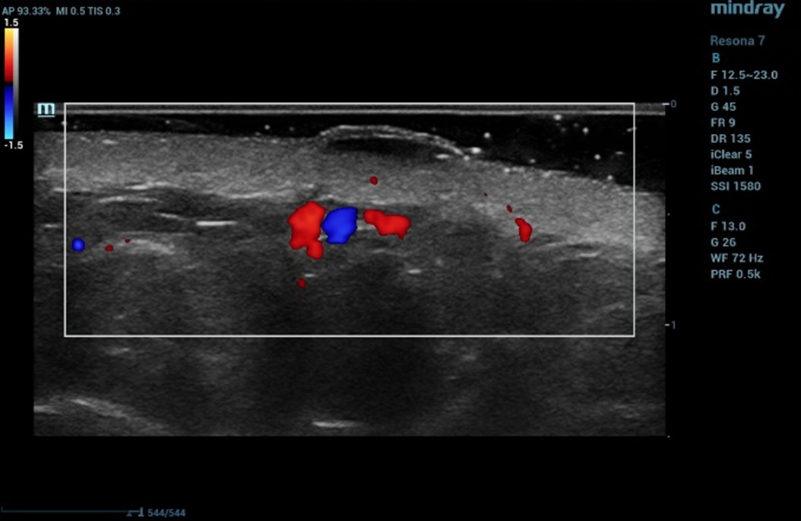

Ultrasound examination of the nevus was performed on the Resona 7 ultrasound machine (Mindray, China) using the high frequency linear transducer L20-5U. When the transducer is placed in the projection of the visible nevus of the left lateral surface of the anterior abdominal wall, an anechogenic oval-shaped mass, located under the epidermis, significantly protruding above the surface and deforming the epidermis outward, with clear even bounds, homogeneous echogenicity, without spreading into the dermis in depth, is visualized. The dermis is homogeneous with increased echogenicity (Figure 5). Blood flow is not registered inside the nevus in the Color Doppler mode (Figure 6).

Ultrasound examination of the nevus in Color Doppler mode

Figure 6. Ultrasound examination of the nevus in Color Doppler mode